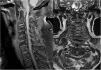

Case descriptionThis is an 80-year old male patient, hypertensive and long-time smoker. He presents with symptoms evolving over 5 months, with the presence of paresthesia and hypoesthesia of the fingers and forearms. The patient develops progressively dysesthesia of the lower extremities and is unable to walk due to weakness. He has been bed-ridden for 2 months and became dependent for all his activities of daily living. He experienced a fall and hence was referred to a 4th level hospital. The physical examination revealed symmetrical quadriparesis, generalized hyperreflexia, bilateral Babinski, generalized hypoesthesia with C3 level of sensitivity, and bilateral Hoffman. The plain MRI of the spine (Fig. 1) showed evidence of odontoid pannus causing acquired canal narrowing with severe stenosis of the spinal canal and bone marrow compression with acute myelopathy signs. Other findings included bone marrow edema in the cervical segment of the spine, as well as degenerative changes throughout the segments of the cervical spine. The laboratory analyses resulted in a positive rheumatoid factor (113IU/ml), negative anti-cyclic citrullinated peptide (4.1U/ml), acute phase reactants (globular sedimentation rate, C-reactive protein) and negative antinuclear antibodies. The hand and foot X-rays showed no bone erosions, with osteo-arthrosis changes. The patient underwent decompression and C1–C2 arthrodesis with good postoperative evolution and partial recovery of his motor deficit. Three weeks after admission the patient was discharged on a treatment with prednisolone 10mg, sulfasalazine 1000mg and leflunomide 20mg per day. The patient experienced clinical improvement and was able to walk unassisted.

Images are critical to assess the axial involvement in RA. The cervical spine radiograph is useful in asymptomatic patients. Dynamic projections are needed to identify subluxations, however these images fail to identify any soft tissue abnormalities that may compromise the spinal canal, as it is the case with our patient with pannus-associated myelopathy. This drawback is also present in CT images and hence MRI becomes the modality of choice in symptomatic patients, due to its ability to detect soft tissue and bone marrow abnormalities.4